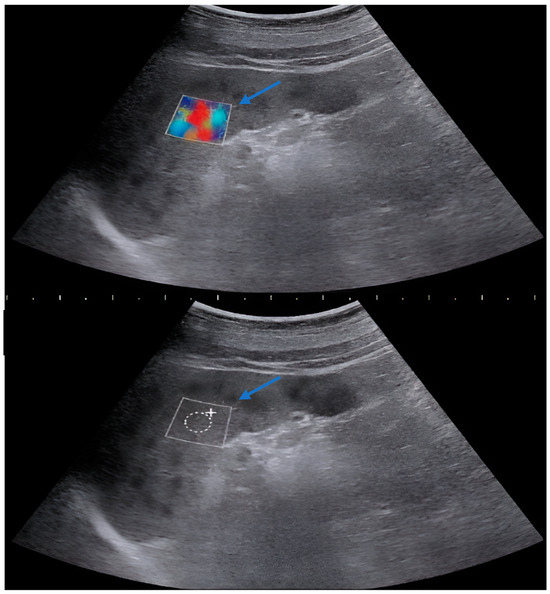

2.2. Methods